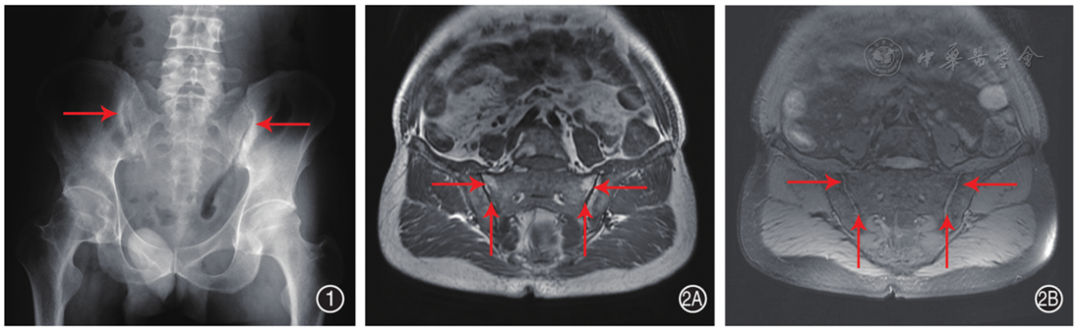

符合纳入标准的有29例IBD伴发ax-SpA患者,占同期住院IBD患者1.84%(29/1 575)。排除7例临床资料不完整和1例IBD诊断年龄小于14岁患者,最终纳入患者21例,其中男性14例(66.7%),女性7例(33.3%);IBD确诊年龄29(24,42)岁;UC 10例,CD 11例。21例患者均行骶髂关节影像学检查,存在骶髂关节炎性改变( 图1 和 图2 ),均为AS。11例(52.4%)患者ax-SpA先于IBD确诊,间隔时间84(34,156)个月;7例(33.3%)IBD先于ax-SpA确诊,间隔时间54(12,84)个月;3例(14.3%)同时确诊。

图1 32岁男性溃疡性结肠炎患者X线图 可见双侧骶髂关节骨组成形态正常,关节面下骨质硬化,左侧为著(右侧箭头),右侧关节间隙局部狭窄(左侧箭头),左侧关节间隙未见明显狭窄

图2 42岁男性克罗恩病患者磁共振图 2A、2B:分别为T 1、T 2压脂信号,双侧骶髂关节对称,双侧骶髂关节组成骨对位关系正常;双侧骶髂关节面毛糙,骨质内见斑点状长T 1长T 2信号,双侧骶髂关节面下见多发斑片状短T 1信号(图2A横向箭头),压脂相呈低信号(图2A、2B纵向箭头),双侧骶髂关节间隙狭窄(图2B横向箭头)